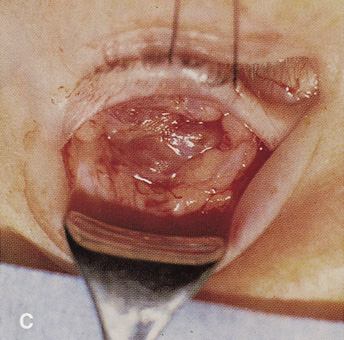

Fig. 16. A. Patient with right orbital cellulitis. B. Coronal CT scan demonstrating subperiosteal abscess formation from frontal and ethmoidal sinusitis. C. Frontoethmoidal orbitotomy incision marked for abscess drainage.

The periosteum is exposed and incised with a Freer elevator and then is reflected off the bone posteriorly. It is generally quite adherent to the curved contour of the medial canthal bones, especially at the medial canthal tendon. The anterior lacrimal crest is encountered inferiorly. Care should be taken not to damage the lacrimal sac with the elevator. The posterior lacrimal crest is visible behind the sac. Adequate mobilization of the periosteal connections to the anterior lacrimal crest gives a large area of exposure. The periosteal elevation is carried superiorly in the area of the trochlea. Elevation of the periosteum opens the subperiosteal space. Blood or pus caused by fracture or infection, if present in this space, is encountered at this point.

Elevation of the periorbita along the medial orbital wall posterior to the lacrimal sac progresses easily. Orbital fractures involving the thin ethmoid bone are seen at this point. The anterior ethmoidal artery is seen at the junction of the ethmoidal and frontal bones where the orbital roof meets the medial orbital wall (see Fig. 7). Usually it is found on a line extending posteriorly from the superior border of the medial canthal tendon. This artery either should be thoroughly cauterized with the bipolar cautery or clipped with a vascular clip before cutting. As the dissection in the subperiosteal space moves posteriorly, the orbit narrows. The posterior ethmoidal artery is identified. This is a reliable landmark for the optic foramen, which lies approximately 5 mm behind the ethmoidal artery.

Indications

The frontoethmoidal medial orbitotomy allows access for a variety of procedures in the subperiosteal and peripheral surgical spaces and sinuses (Fig. 17). Its main use is for processes involving both the frontal or ethmoid sinuses and the orbit. Entrance into the subperiosteal space is obtained easily. Drainage of subperiosteal blood or pus occurs as the space is entered.